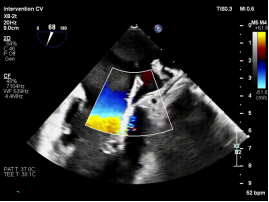

【图片2-5:术中TEE、夹持瞬间、术后效果图】

术后即刻评估显示,患者二尖瓣反流由重度(4+)降至轻度(1+),跨瓣压差维持在理想范围,肺静脉血流明显改善,手术取得良好效果。